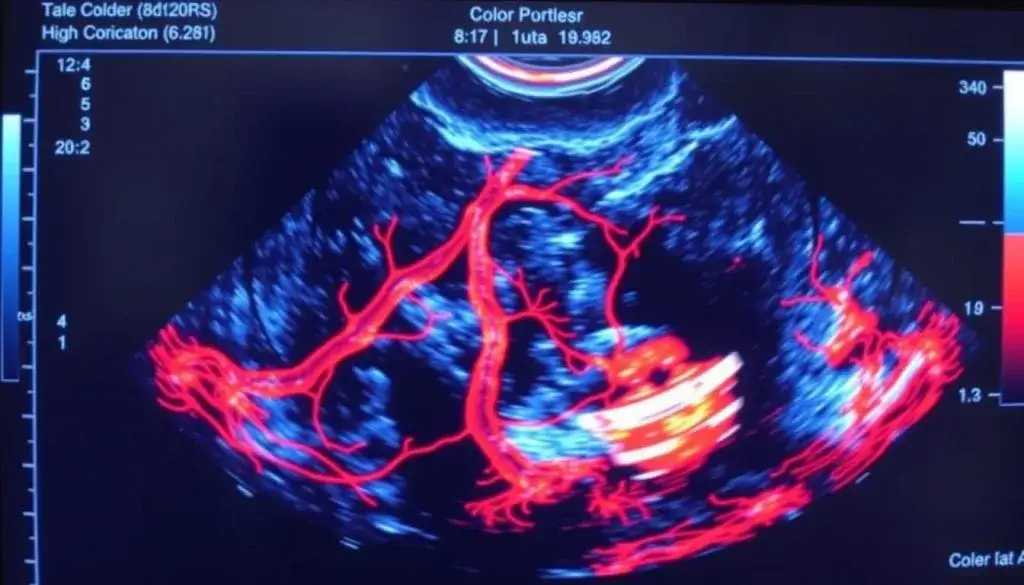

Co lekarz widzi na monitorze? Interpretacja kolorów i wykresów

Obraz na monitorze aparatu USG Doppler jest zazwyczaj wzbogacony o dodatkowe informacje. Przepływ krwi często jest przedstawiany za pomocą kolorów na przykład czerwony może oznaczać przepływ w kierunku głowicy, a niebieski w kierunku przeciwnym. Oprócz tego, na ekranie pojawiają się wykresy, które szczegółowo pokazują prędkość przepływu w danym punkcie naczynia. Analizując te dane wizualne, lekarz jest w stanie ocenić, czy przepływ jest prawidłowy, czy też występują w nim jakieś zaburzenia, takie jak zwężenia, niedrożności czy nieprawidłowe kierunki przepływu.